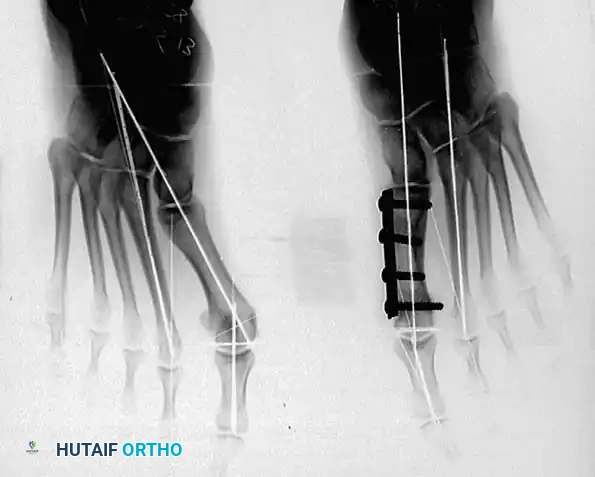

• Grasp the hallux in one hand and displace the proximal remnant medially so that, under direct vision, two longitudinal 0.062-inch Kirschner wires can be inserted.

• Hold the interphalangeal joint straight while drilling the wires from proximal to distal, emerging a few millimeters plantar to the nail plate.

• Return the foot to the corrected position, and drill the wires into the metatarsal head.

• While holding the metatarsal as far laterally as possible, cross the joint, and drive the wires out the plantar cortex just proximal to the head, while holding the hallux in 10 to 15 degrees of extension, neutral abduction, adduction, and rotation, and no translation dorsally or plantarward on the metatarsal head. The wires should penetrate only 2 to 3 mm past the cortex to avoid tenderness over the wires with weight bearing.

• When the sesamoid has been removed, insert two 0.062-inch Kirschner wires retrograde from the tip of the toe 2 to 3 mm plantar to the nail bed, leaving about 5 to 7 mm of the pins exposed at the base of the phalangeal remnant to help align the phalanx on the metatarsal before antegrade passage of the pins into the metatarsal (Fig. 78-31F).

LATERAL DISPLACEMENT OF THE FIRST METATARSAL

• Push the metatarsal laterally several times. Occasionally, this does not move the metatarsal, but some lateral mobility usually is present.

• While standing next to the patient looking distally at the dorsum of the foot, dorsifl ex the ankle to neutral.

• Viewing the foot as the patient would, hold the fi rst metatarsal fi rmly, and move its distal end laterally. Hold this position with one hand, and use the other hand to place the hallux on the metatarsal head and out to length.

• While holding the fi rst ray straight with the foot vertical, have an assistant insert the wires from distal to proximal (Fig. 78-31G). Often these wires, which run through the fi rst metatarsal and hallux, hold the fi rst ray straight, and most of this correction is maintained after the wires have been removed.

• Close the capsule with a purse-string suture as previously described in the original technique (Fig. 78-31H to J).